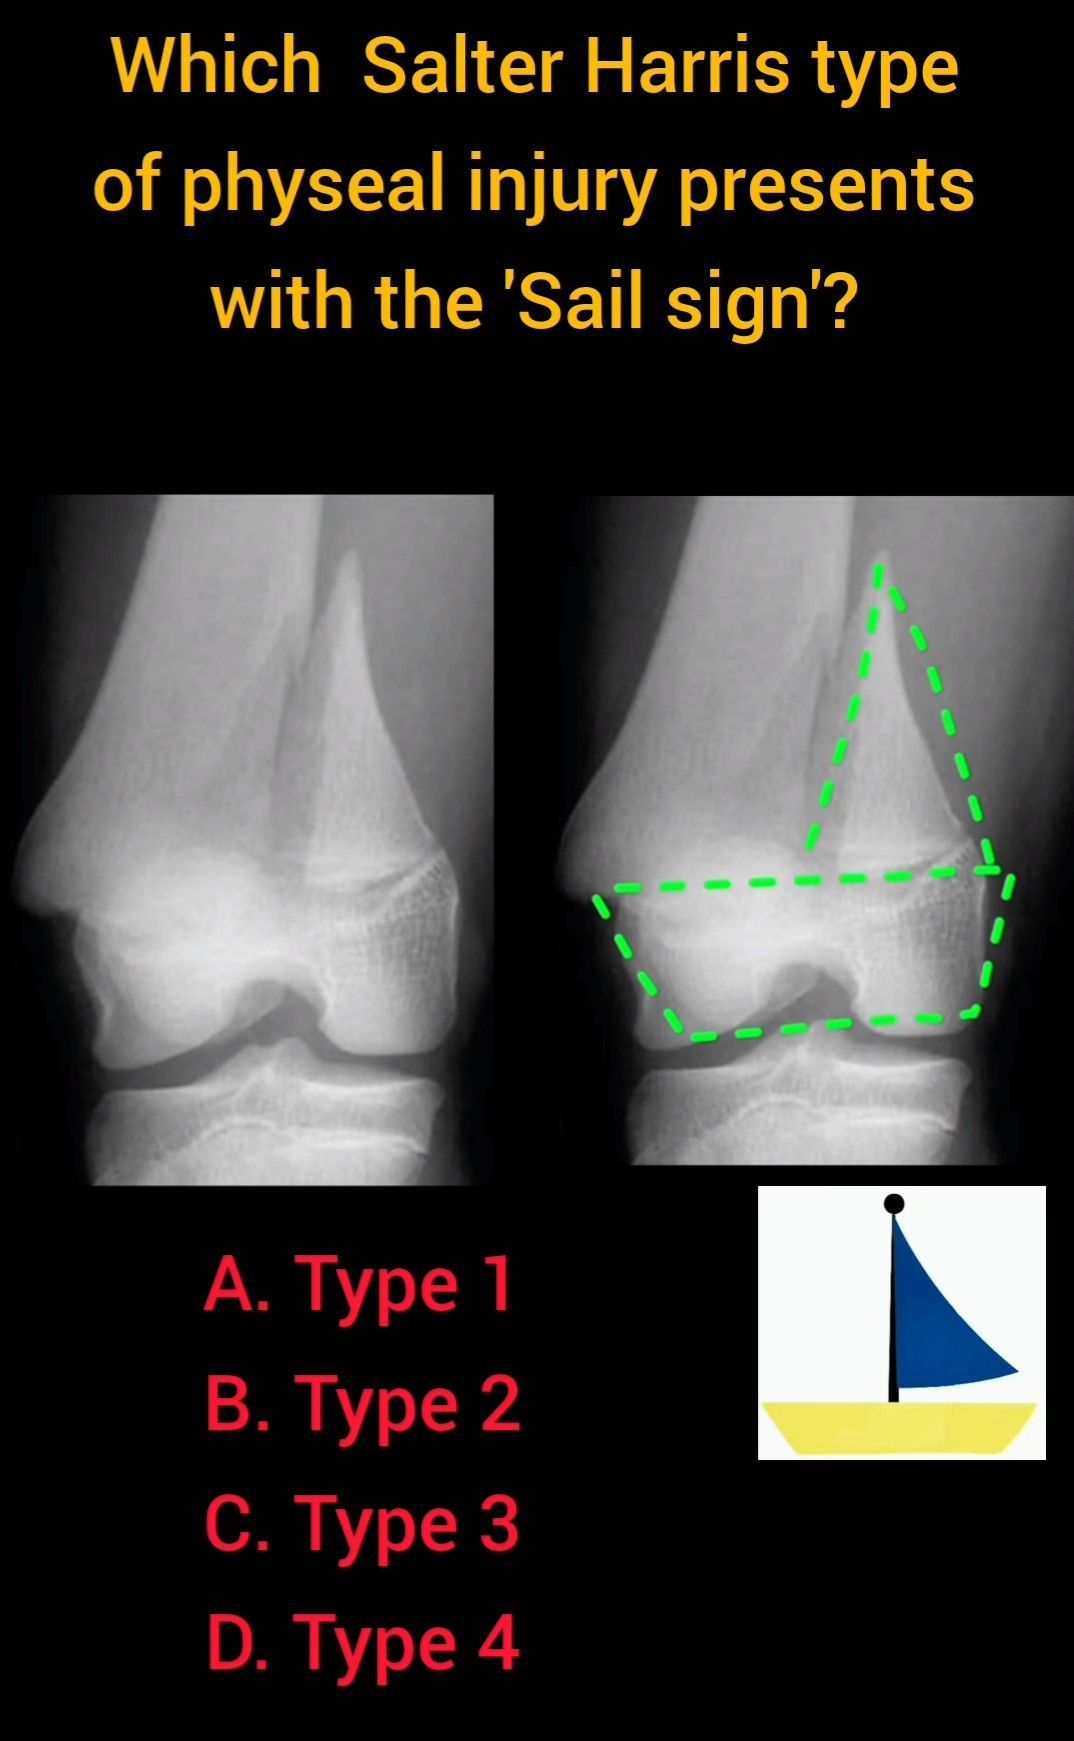

Sail Sign

Which answer fits the description?

Sailsign